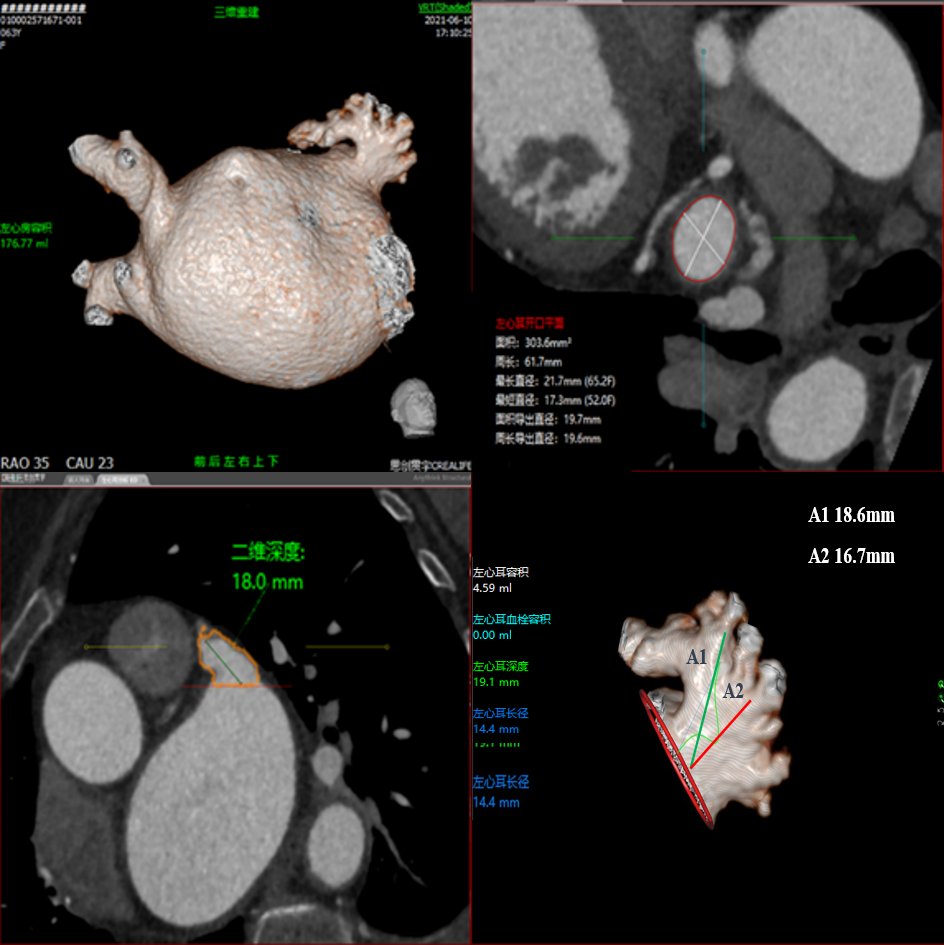

术前CT评估

行CT评估后左心耳内未见血栓,左心耳呈反鸡翅型,开口呈椭圆形,最短径17.3mm,最长径 21.7mm,三维深度19.1mm,二维深度 18.0mm。分析后提示宜选择24mm Watchman封堵器,但若采用下叶进行封堵,深度较浅,应首选上叶做为轴线进行封堵。

采用CT模拟最佳左心耳封堵工作体位,发现在RAO30 CAU25时左心耳展开较常规体位更好。